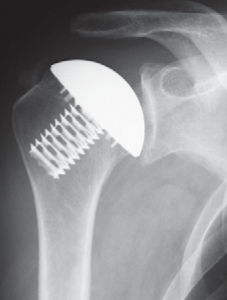

Bei jüngeren Patienten mit umschriebenen schweren Knorpeldefekten, die ohne Behandlung zur schweren Arthrose führen, werden so genannte Teil-Gelenkflächen (Hemi-CAP®) in die defekte Knorpelzone geschraubt (Abb. 45). Bei umschriebenen kleineren 4° Knorpelschäden besteht die Möglichkeit zur autologen Knorpelzelltransplantation. Dabei wird arthroskop. in einer ersten Operation Knorpel an der Schulter entnommen und für 6 Wochen im Labor angezüchtet. Der fertig gezüchtete Knochen wird dann in einem zweiten Eingriff in den Defekt eingepflanzt, der an dieser Stelle dann als vollwertiger Knorpel einwächst.